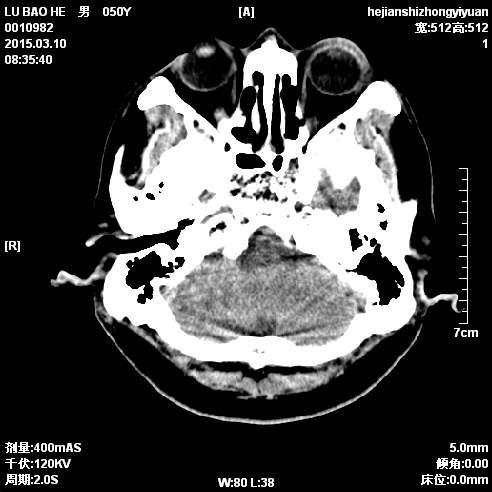

CT50048:头疼数日

头疼数日

小脑占位,MRI或增强

考虑右侧小脑占位性病变,建议增强扫描或MRI检查

考虑右侧小脑半球占位性病变,建议增强扫描或MRI检查。

小脑部占位病变,首先考虑髓母细胞瘤。

建议核磁,考虑小脑右侧转移或髓母